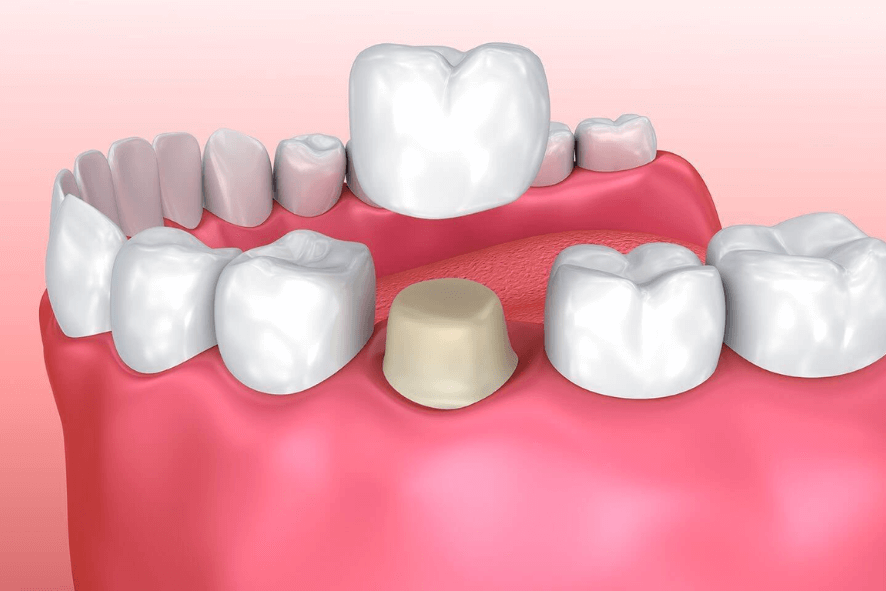

Coroas sobre dente

“Capas” que recobrem dentes danificados, restaurando forma, função e estética.

👉 Garantem proteção ao dente natural que perdeu muito estrutura e permite recuperar tanto a mastigação quanto a aparência do sorriso.